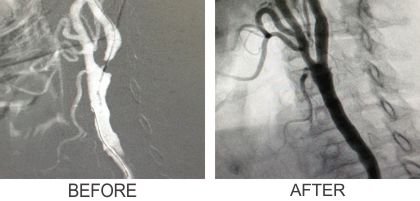

1. Coil Embolisation

3. Carotid Angioplasty